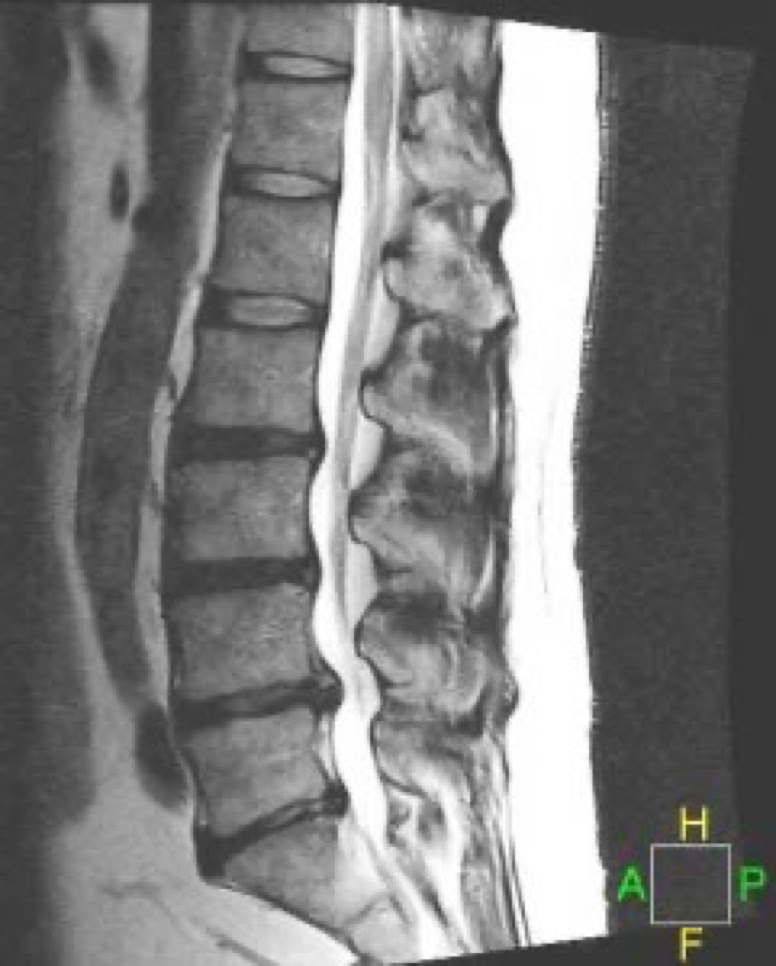

A herniated disc may be diagnosed after a complete history and comprehensive physical exam. In addition, several diagnostic tests can be used. Imaging studies at the Virginia Spine Institute are usually a first step in understanding spine pathology. These include standing and bending X-rays to evaluate spinal alignment, stability and disc space height. Your doctor will determine whether additional tests are needed. An MRI is the standard imaging to assess disc and nerve pathology. An EMG may be used to determine which specific nerves are involved and the extent of possible nerve damage.

LUMBAR DISC HERNIATIONS ON MRI